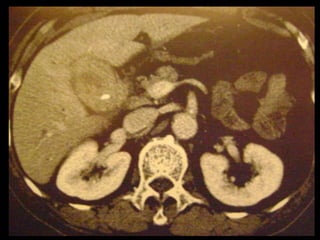

Colecistite aguda

Causada por obstrução do ducto cístico ou do colo

da vesícula biliar, que leva à inflamação da parede

da VB e ao aumento da pressão intraluminal;

Sinais e sintomas clínicos da colecistite são

inespecíficos e em 60-85% dos pacientes

examinados em busca de colecistite foi constatado

queos sintomas resultavam de outras causas.

A maioria dos casos(90%) é provocada por cálculos

biliares impactados.

US é a modalidade de imagem de escolha;

Em geral, a TC é realizada para avaliar pacientes

com suspeita de complicações do quadro de

colecistite aguda, como perfuração por exemplo.

Achados na TC: cálculos biliares, espessamento da

parede, alterações inflamatórias

perivesiculares, bile com alta

atenuação, borramento da interface VB-fígado e

aumento transitório da atenuação do fígado

perivesicular;